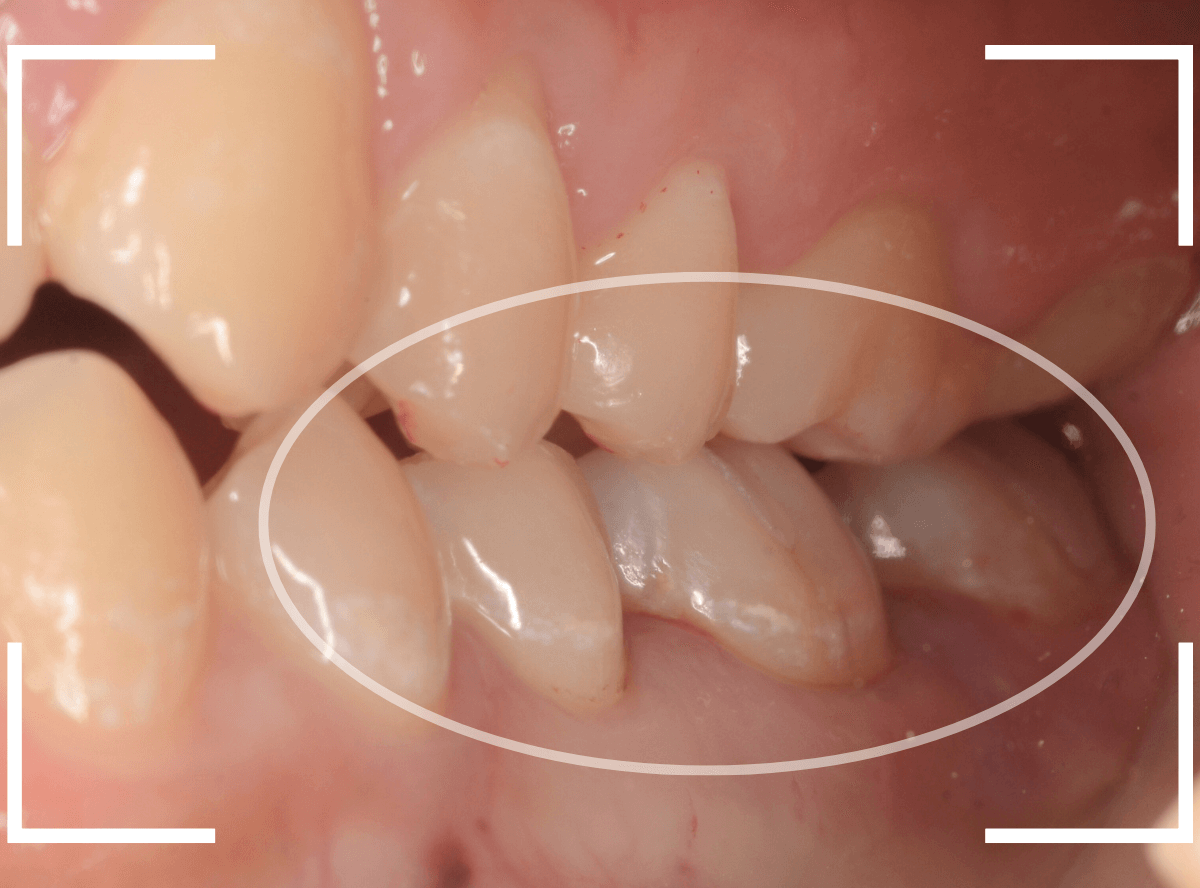

下の奥歯が虫歯になった患者さんのケースです。

〇部が虫歯の部分です。

写真で見てわかるように、常に舌が歯に触っているような状況です。

このような場合、虫歯を見つけづらいですし、治療の難易度もあがります。